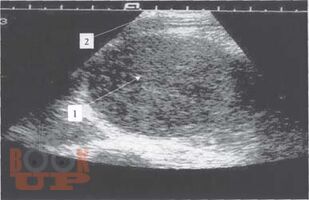

Томографическая диагностика опухолей и опухолевидных образований яичника у девочек

Диагностика и лечение опухолей и опухолевидных образований яичников у девочек и подростков является актуальной проблемой. Совершенство методов диагностики при данной патологии, хорошо зарекомендовавших себя во многих областях медицины, способствует внедрению их в клинику детской гинекологии, онкогематологии, детской хирургии.

Разнообразие средств диагностики, отличающихся по физическим данным и разрешающим способностям, а также по стоимости аппаратуры и самих исследований, часто ставит врача перед сложной проблемой определения необходимого минимума применяемых методов, последовательностью их выполнения и интегрирования результатов разных исследований в единую диагностическую концепцию.